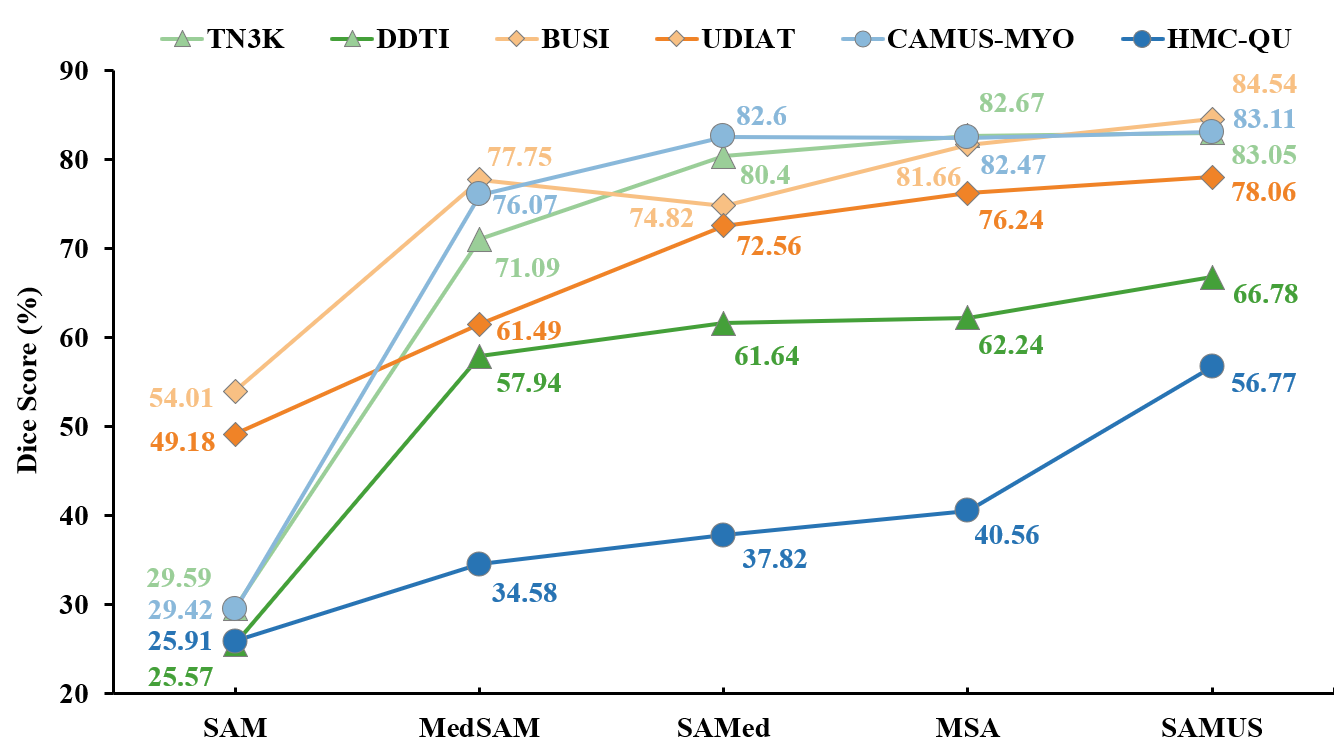

Generalization ability: Comparison of different foundation models on unseen domains is summarized in Fig. 6. In general, the generalization performance of foundation models trained on US30K in the medical image segmentation tasks is far better than that of the original SAM. In terms of the three pairs of segmentation tasks, namely thyroid nodule segmentation, breast cancer segmentation, and myocardium segmentation, all foundation models encounter severe performance degradation on myocardium segmentation and generalize well on breast cancer segmentation. SAMUS consistently achieves the best performance across all three unseen datasets, leading to superior Dice scores of , , and for the segmentation of thyroid nodule, breast cancer, and myocardium, respectively. It underscores the exceptional generalization ability of SAMUS, outperforming other foundation models consistently and substantially on unseen domains.